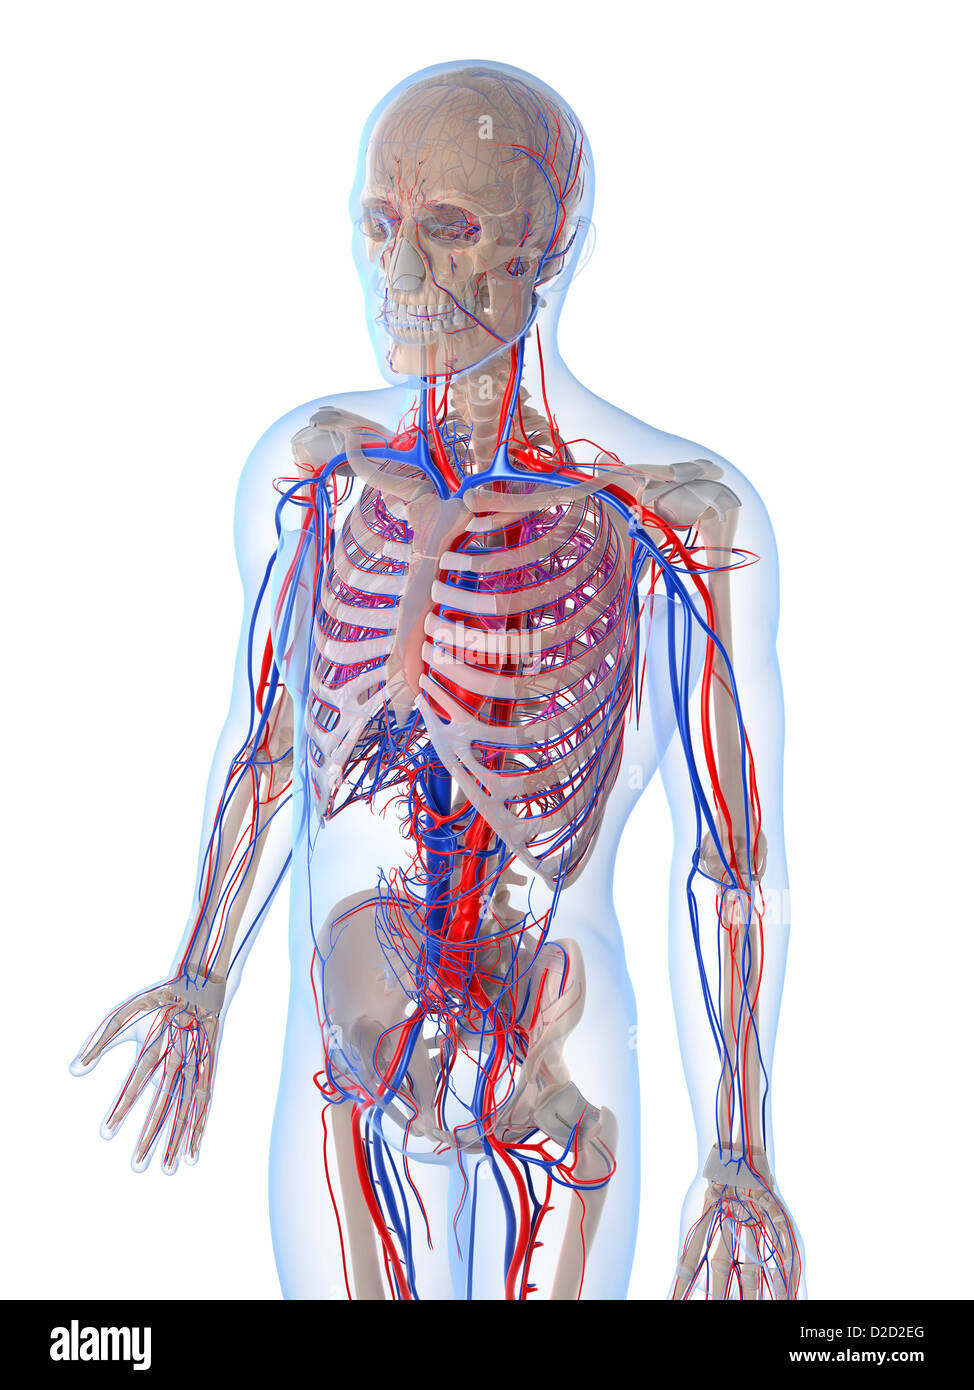

Анатомия человека: кровеносная система и её связь со скелетом

Раздел: Моменты озарения